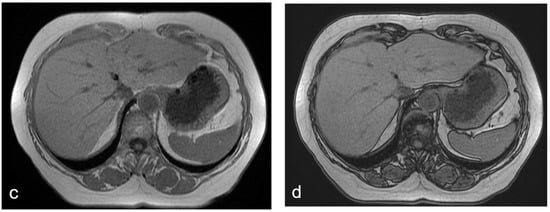

Figure 6.

(a–d) A 52-year-old woman with hepatic metastases from colon cancer undergoing neo-adjuvant chemotherapy with folinic acid, 5-fluorouracil, oxaliplatin, and irinotecan (FOLFOXIRI). After chemotherapy, a new centimetric lesion appeared in segment 7 (arrow). The lesion was not appreciable in the T2-weighted image (a) or in the DW-MRI image, with b-values of 1000 s/mm2 (b). After the administration of Gd-EOB-DTPA, the lesion appeared hyperintense in the arterial phase image (c) and slightly hypointense in the hepatobiliary phase image (d) and was not easily recognizable from the surrounding hepatic parenchyma, which is markedly inhomogeneous and suggestive of SOS. The findings are consistent with an NHR lesion.

NRH appears hypointense in the T1-weighted images and hyperintense in the T2-weighted images; the gadoxetic acid-enhanced MRI shows the lesions as slightly enhanced areas in the vascular phase and as hypointense areas in the HB phase; and the absence of diffusion restrictions in DW-MRI excludes the possibility of liver metastases [6,44,45,46] (Figure 6).

NRH is characterized by regenerative nodules usually > [3] mm in size. Concerning pathophysiology, NRH is believed to be secondary to SOS-induced changes in intrahepatic blood flow, leading to atrophic hypoperfused areas intermingled with hyperperfused regenerative areas [1,2,20]. NRH is generally considered hepatocytic hyperplasia with little pathological significance. In fact, NRH is known to regress up to nine months after the last cycle of oxaliplatin-based chemotherapy [27].

However, in its more widespread and advanced forms, NRH nodules may lead to compression and atrophy of the surrounding liver parenchyma, portal hypertension, and increased postoperative morbidity [4].

A prevalence of NRH of approximately 15–20% has been reported after oxaliplatin-based chemotherapy [2,4,20,27,43]. On the contrary, the association of bevacizumab has a protective effect and reduces the prevalence of NRH [1,2,20,27]. However, no correlation was demonstrated between NRH and the number of chemotherapy cycles [2,4,43].